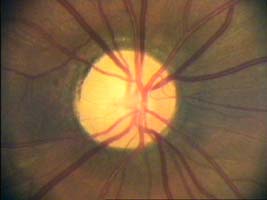

Velikost terče

Tento terč má širokou cirkulární peripapilární atrofii, která opticky vytváří falešný dojem širokého neuroretinálního lemu, zvláště nasálně.